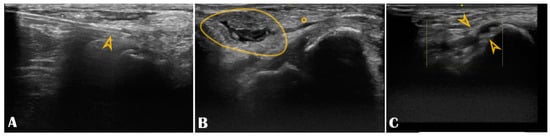

Figure 6.

Panel (A): The puncture needle is clearly seen in the longitudinal axis (arrowhead); Panel (B): Hematoma (circle) compressing the distal radial artery (asterisk); Panel (C): The distal radial artery is with stenotic atherosclerotic plaques (arrowheads).